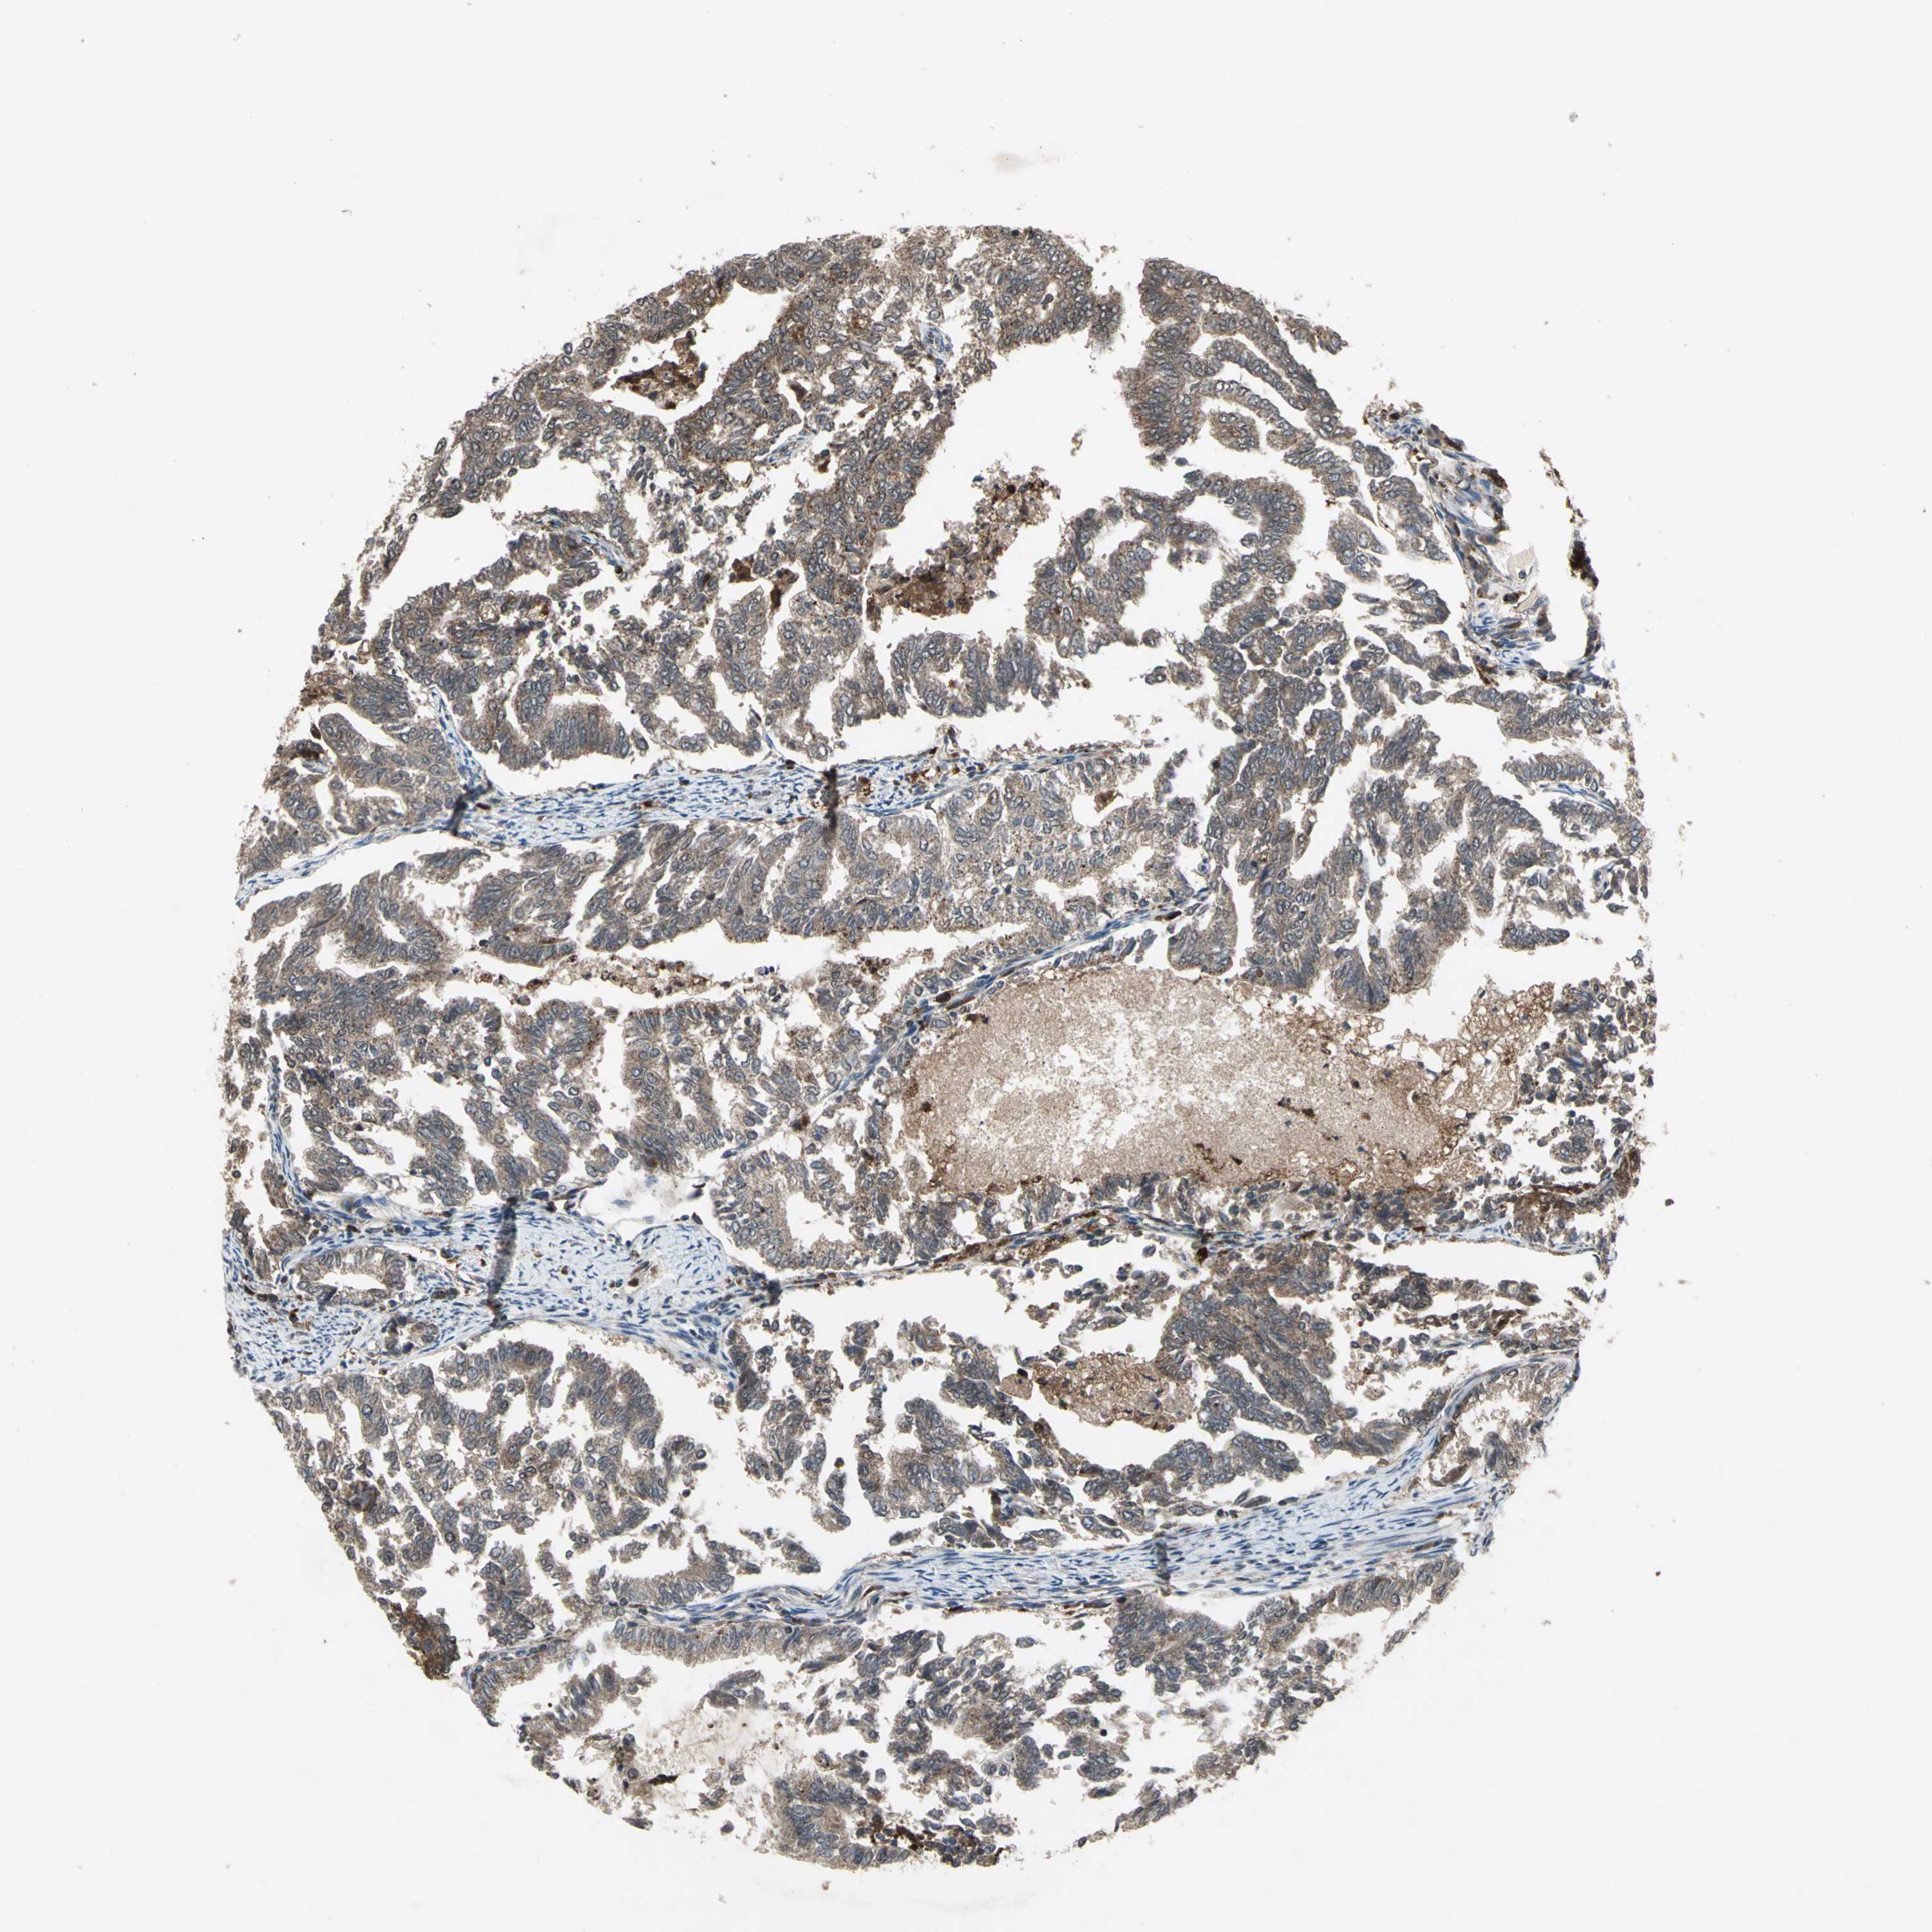

ENDOMETRIAL CANCER - Protein expressioni

A mouse-over function shows sample information and annotation data. Click on an image to view it in a full screen mode. Samples can be filtered based on level of antibody staining by selecting one or several of the following categories: high, medium, low and not detected. The assay and annotation is described here.

Note that samples used for immunohistochemistry by the Human Protein Atlas do not correspond to samples in the TCGA dataset.

Antibody stainingi

Antibody staining in the annotated cell types in the current human tissue is reported as not detected, low, medium, or high, based on conventional immunohistochemistry profiling in selected tissues. This score is based on the combination of the staining intensity and fraction of stained cells.

Each image is clickable and will lead to virtual microscopy that enables deeper exploration of all samples and also displays staining intensity scores, fraction scores and subcellular localization as well as patient and tissue information for each sample.

Antibody HPA049074

Antibody HPA054496

Antibody CAB006853

Antibody CAB015948

Staining

High

Medium

Low

Not detected

Intensity

Strong

Moderate

Weak

Negative

Quantity

>75%

75%-25%

<25%

None

Location

Nuclear

Cytoplasmic/membranous

Cytoplasmic/membranous,nuclear

Adenocarcinoma, NOS

Carcinoma, NOS

Adenocarcinoma, metastatic, NOS

Neoplasm, malignant, NOS